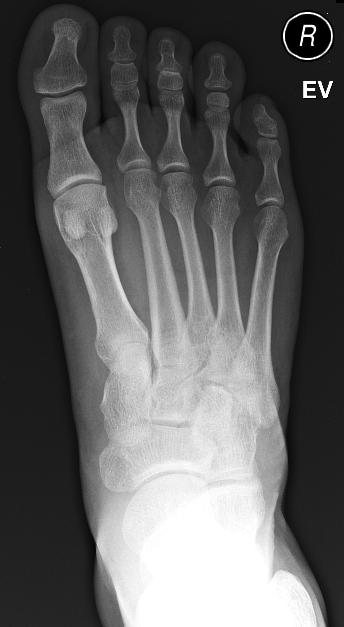

I had recently been hobbling around for about a week and a half (just before I started running again). I stepped on some glass that managed to embed itself in my foot. I bounced from clinic to clinic in search of the necessary images and scalpels. In the end, the x-rays revealed nothing and the surgeon just went for a dig. The glass is now out and my foot is pretty much healed.

This is what my foot looks like naked.